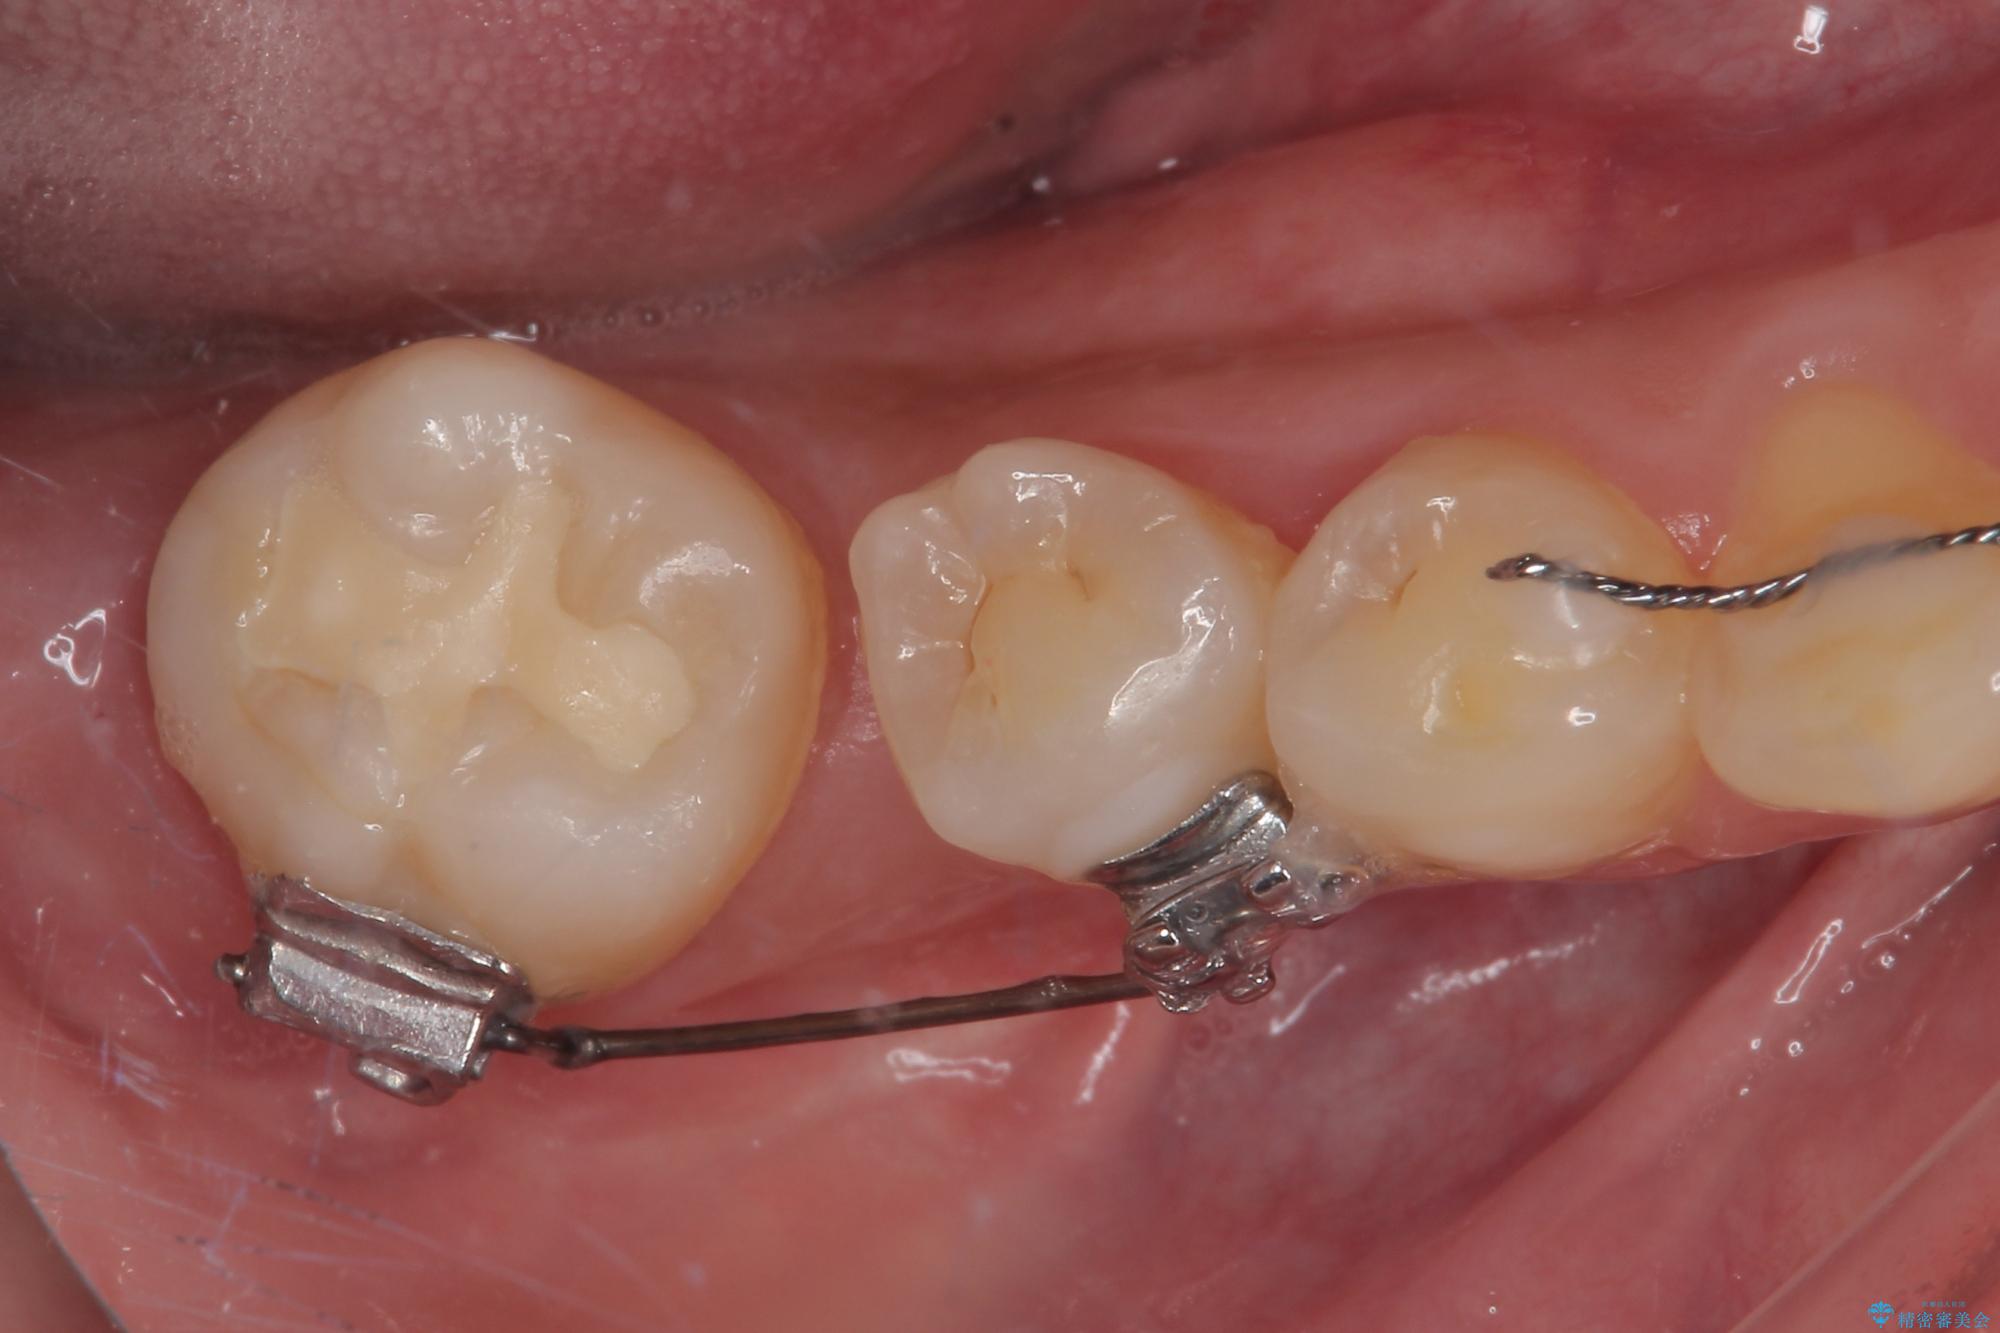

隙間の空いた奥歯 オールセラミッククラウンの補綴治療

- 1本欠損したままの奥歯の治療を終えたいとのことで来院された患者様です。

奥歯が1本欠損した状態で矯正治療を行っていたそうですが、どのように治療を終了させるか未決のまま矯正装置を除去してしまい、暫く放置されている状態でした。

理想的には残っている歯のスペースを詰め、最後方にインプラントを埋入することが理想的ではありますが、矯正治療期間や費用の面から、前後に歯を大きくする補綴治療を行うことで対応することとなりました。

矯正装置を長いこと付けていたことで、歯が大きく捻転してしまい、舌に当たる感覚を気にしていらっしゃいましたが、補綴治療により捻転とともに解消することができました。

上顎の最後臼歯と咬み合わせるために前後径が大きくなっており、歯肉周りに汚れが溜まりやすくなるため、日々の清掃と定期的なクリーニングが必要となります。